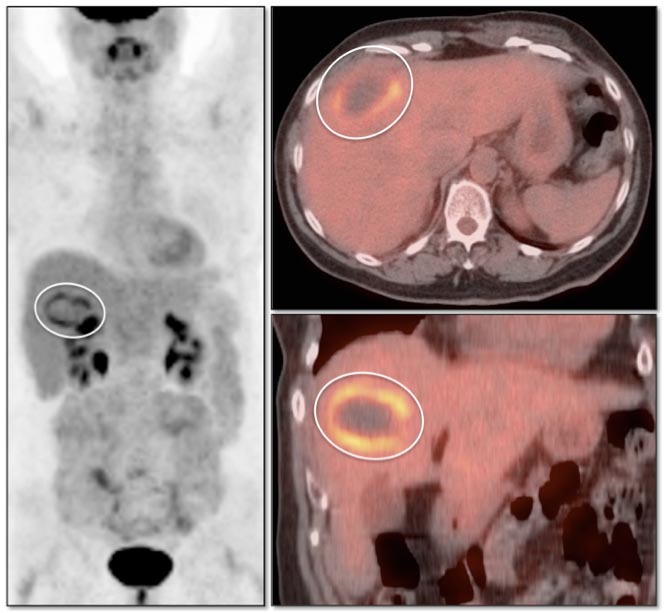

Recurrent/Residual Malignancy:

- Any nodular or focal uptake within or abutting the ablated lesion is highly suspicious for malignancy.